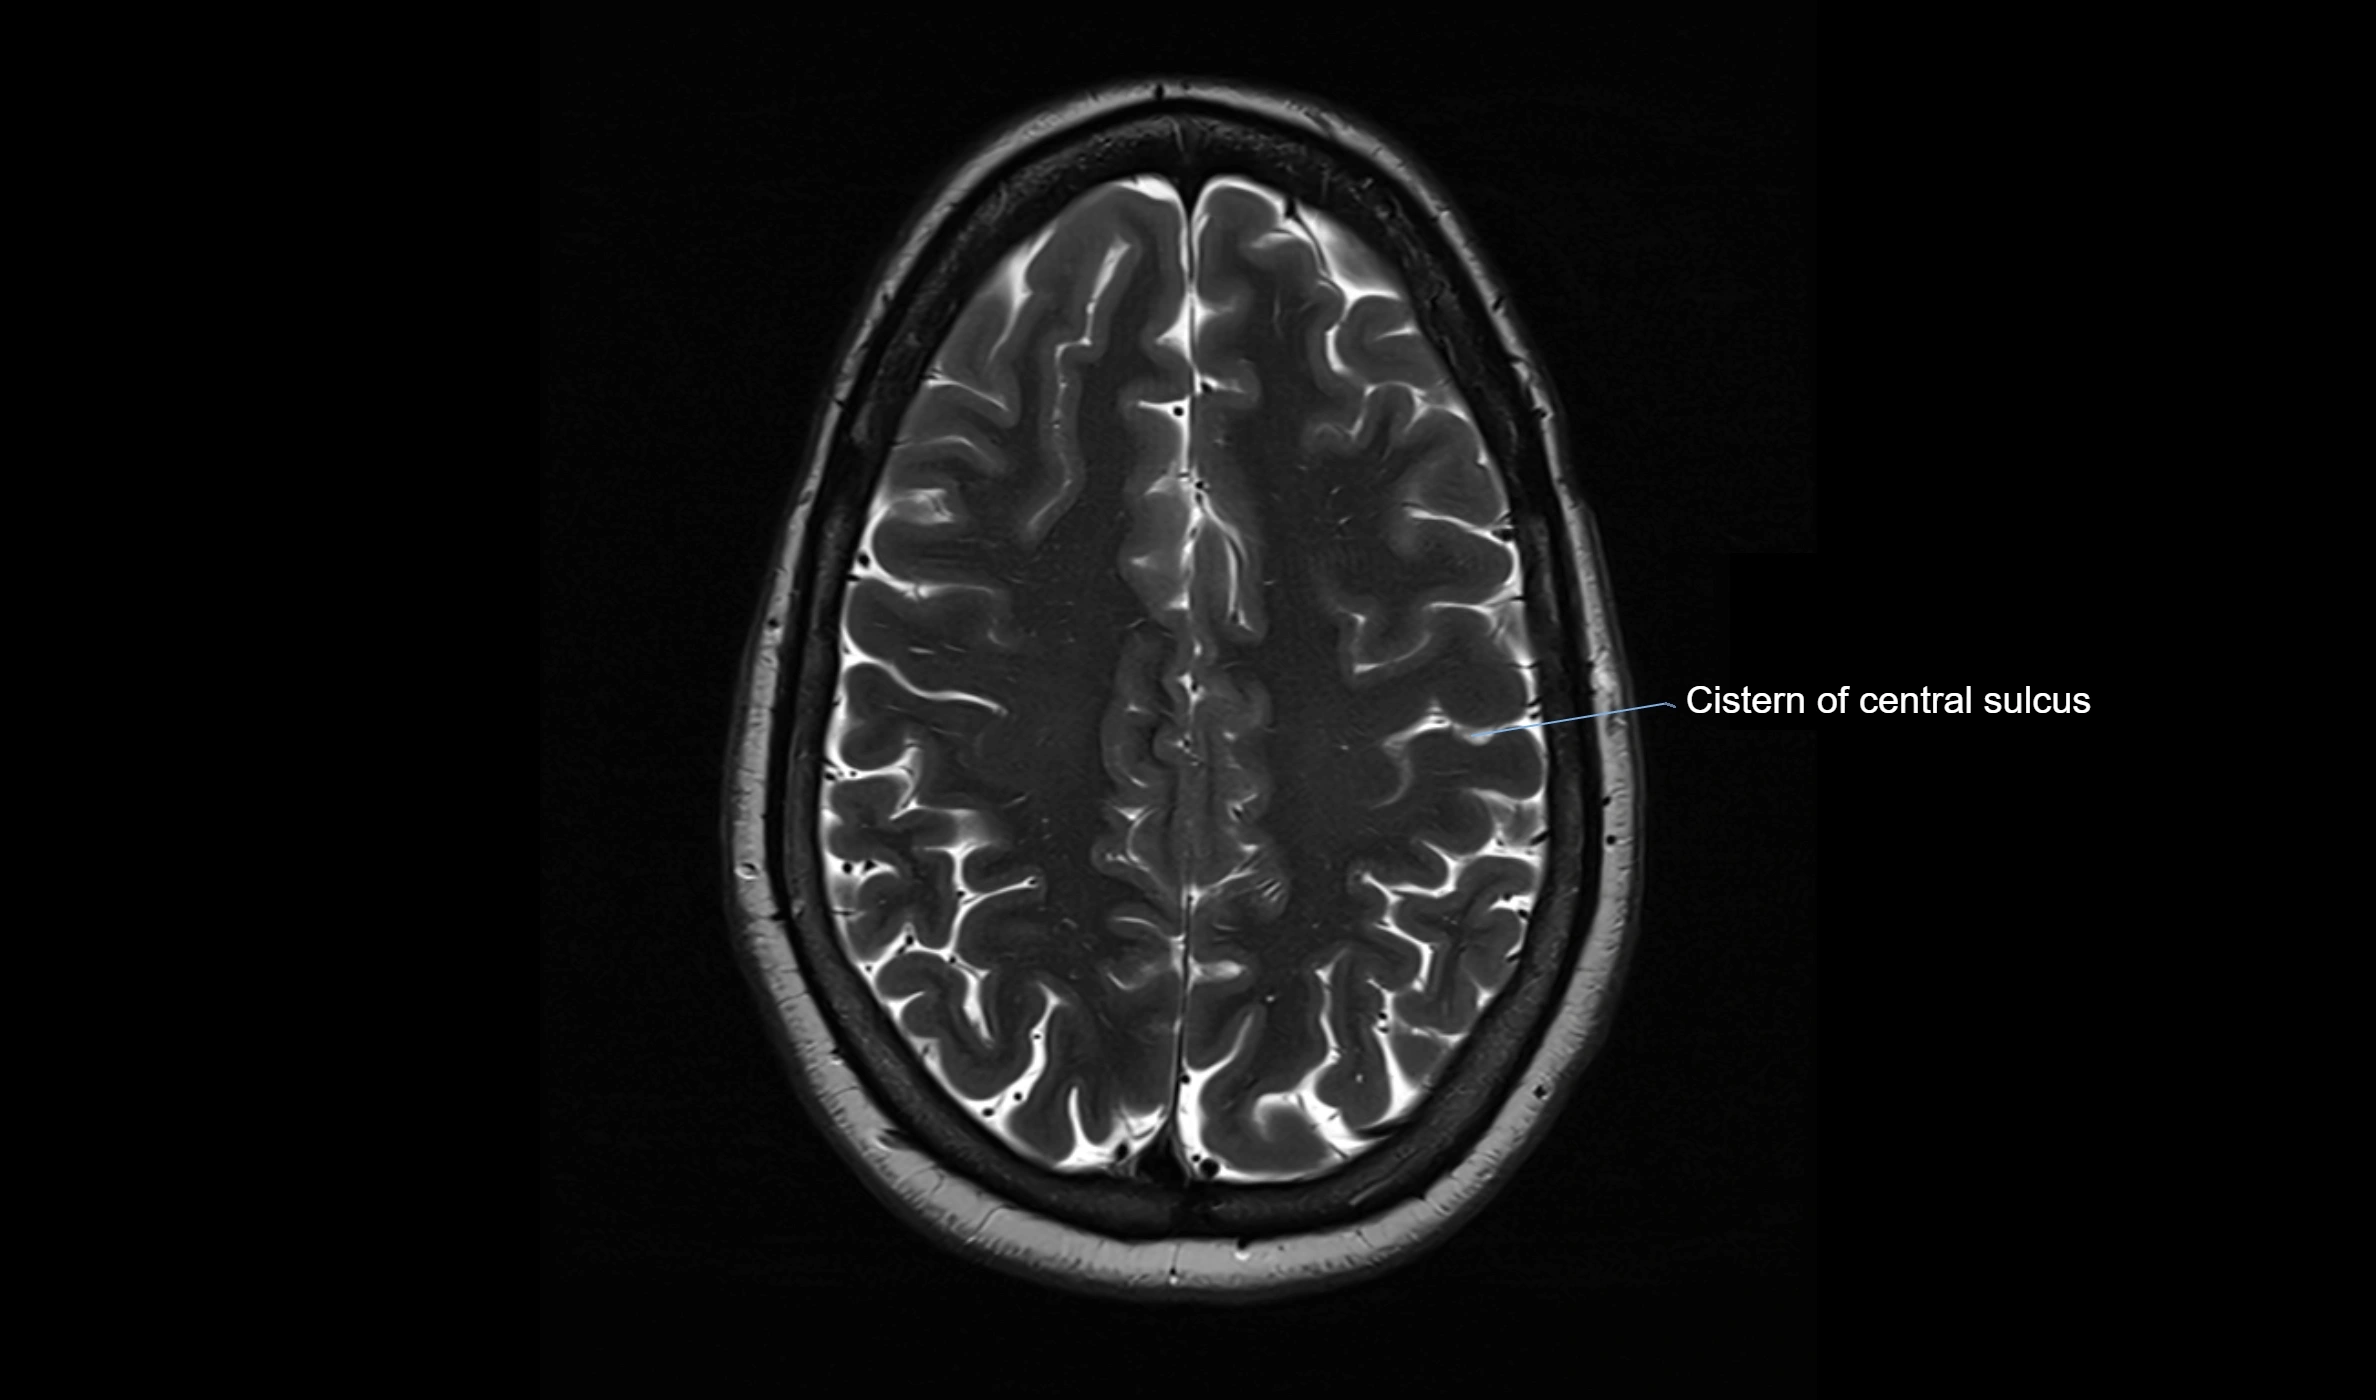

MRI images

image